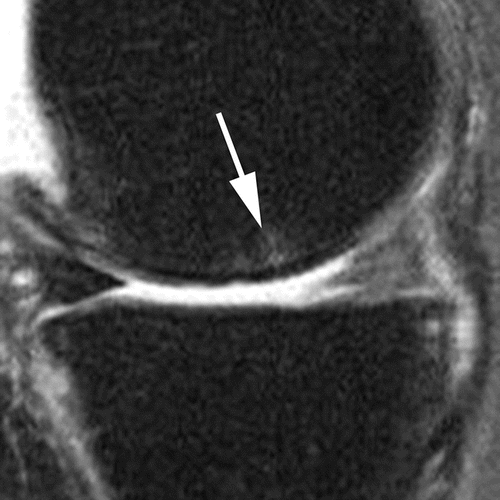

• cartilage morphology and subchondral bone marrow lesions (BMLs) in ​​14 subregions

Subregional joint division using MRI Osteoarthritis Knee Score (MOAKS)

BML assessment according to size

Grade 1

Grade 2

Grade 3